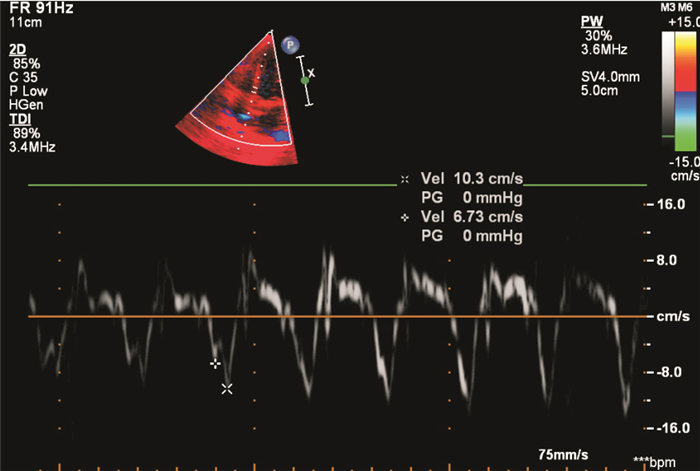

與此同時,在組織多普勒技術監測下可見該患兒二、三尖瓣環e值、a值、e/a值均出現異常,其中二尖瓣環e值為0.047 5 m/s,a值為0.137 m/s,三尖瓣環e值為0.067 3 m/s, a值為0.103 m/s。e/a<1,提示左室舒張功能減退,如圖 2所示。